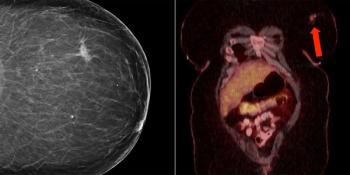

A 52-year-old woman presents with a polypoid endometrial tumor. What is your diagnosis?